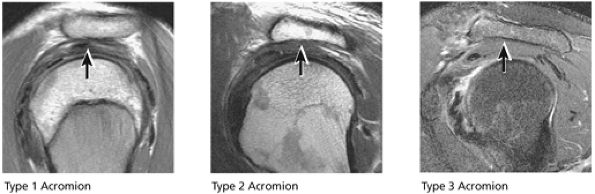

The acromion is classified into several types according to its morphology:

Type 1 (a flat or straight undersurface with a high angle of inclination)

Type 2 (a curved arc and decreased angle of inclination)

Type 3 (hooked anteriorly with a decreased angle of inclination)

Type 4 (upward convexity of the inferior surface) (see also the discussion of the etiology of shoulder impingement syndrome)